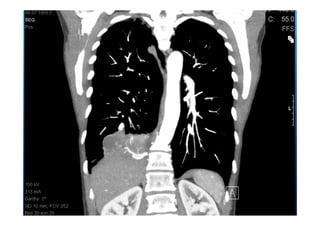

52 jährige Patientin

Gewichtsverlust

Adynamie

Nachtschweiß

Immer wieder Fieber über 12 Monate

Raucherin > 30 packyears

Lungensequester mit

infradiaphragmaler arterieller

Blutversorgung